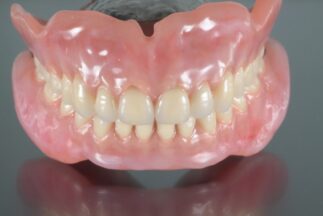

歯肉に自然観を与えた

上下の総義歯